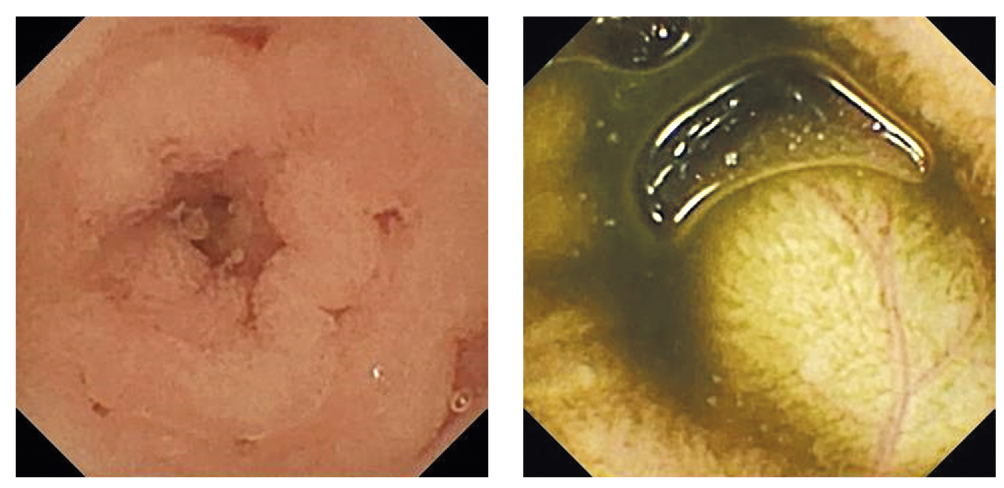

Рис. 3. Видеокапсульные изображения проксимальных (слева) и дистальных (справа) отделов тонкой кишки без следов крови на всем протяжении

Fig. 3. Video capsule images of the small bowel in its proximal part (left) and in distal part (right) without signs of blood throughout

Результаты физикального, лабораторного и инструментального исследования

При поступлении обращали на себя внимание бледность кожных покровов, вялость ребёнка, отставание в физическом развитии: рост 76 см, масса тела 6,3 кг, ребёнок не ползает и не ходит. В общем анализе крови количество эритроцитов 2,72×1012/л, концентрация гемоглобина 82 г/л. Учитывая данные предыдущих методов обследования, исключающие наличие источника кровотечения в верхних и нижних отделах ЖКТ, было принято решение провести ВКЭ тонкой кишки. В условиях эндотрахеальной анестезии при инсуффляции СО2 тонким видеогастроскопом (наружный диаметр вводимой части 5,8 мм) была выполнена диагностическая эзофагогастродуоденоскопия (ЭГДС). Следов крови и источника кровотечения в просвете пищевода, желудка, двенадцатиперстной кишки и доступных осмотру отделов тощей кишки выявлено не было. Стандартным видеогастроскопом (наружный диаметр вводимой части 9,2 мм) с введённым в инструментальный канал эндоскопическим сачком видеокапсула (Olympus) была заведена в нисходящую ветвь двенадцатиперстной кишки (рис. 1). Антенна-пояс фиксирована вокруг живота ребёнка (рис. 2), а записывающее устройство передано маме. Спустя сутки капсула вышла естественным путём через анус ребёнка. При расшифровке ВКЭ следов крови в просвете тонкой кишки, эрозивно-язвенных поражений, патологических новообразований, анатомических аномалий кишечника, сосудистых мальформаций и ангиэктазий выявлено не было (рис. 3).